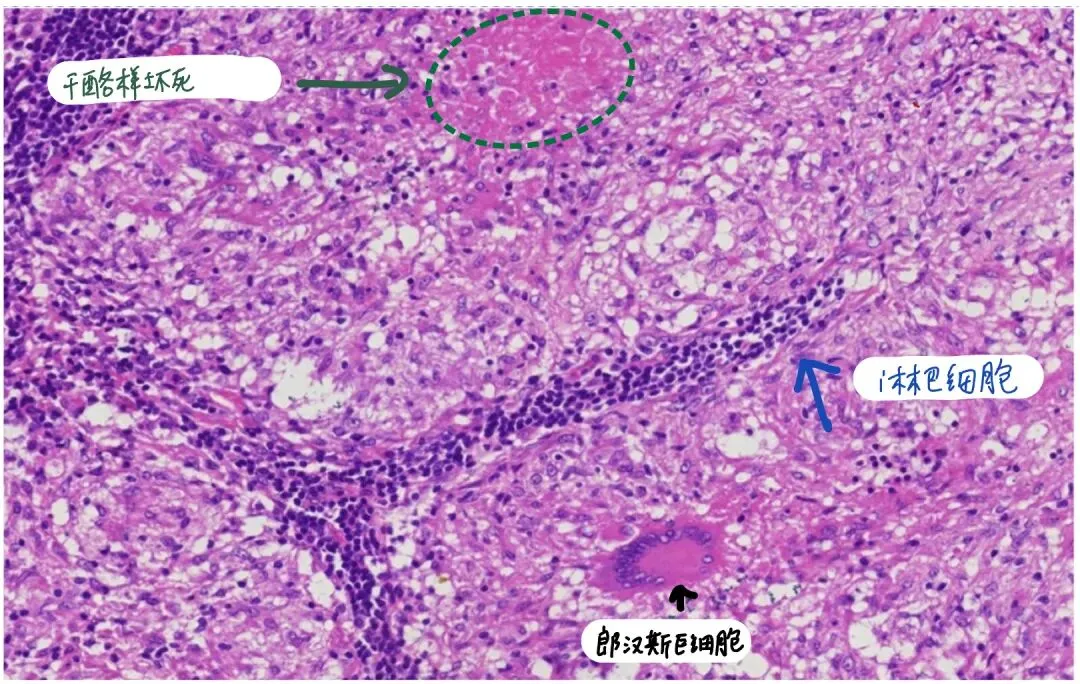

多核巨细胞的细胞核数目可达几十个,甚至几百个;结核结节中的多核巨细胞又称为朗汉斯巨细胞,由上皮样细胞融合而来,其细胞核排列于细胞周边呈马蹄形或环形,胞质丰富;

干酪样坏死周边可见上皮样细胞。

结核可见干酪样坏死、上皮样细胞、朗汉斯巨细胞、淋巴细胞浸润。

总结一下:巨噬细胞转化成上皮样细胞   → 巨噬细胞或上皮样细胞融合 → 形成多核巨细胞 → 其中一种(朗汉斯巨细胞)的细胞核排列成马蹄环样,理解就是朗汉斯巨细胞是多核巨细胞的一种类型,主要见于特定的感染性或免疫性肉芽肿疾病,比如提示结核等疾病;